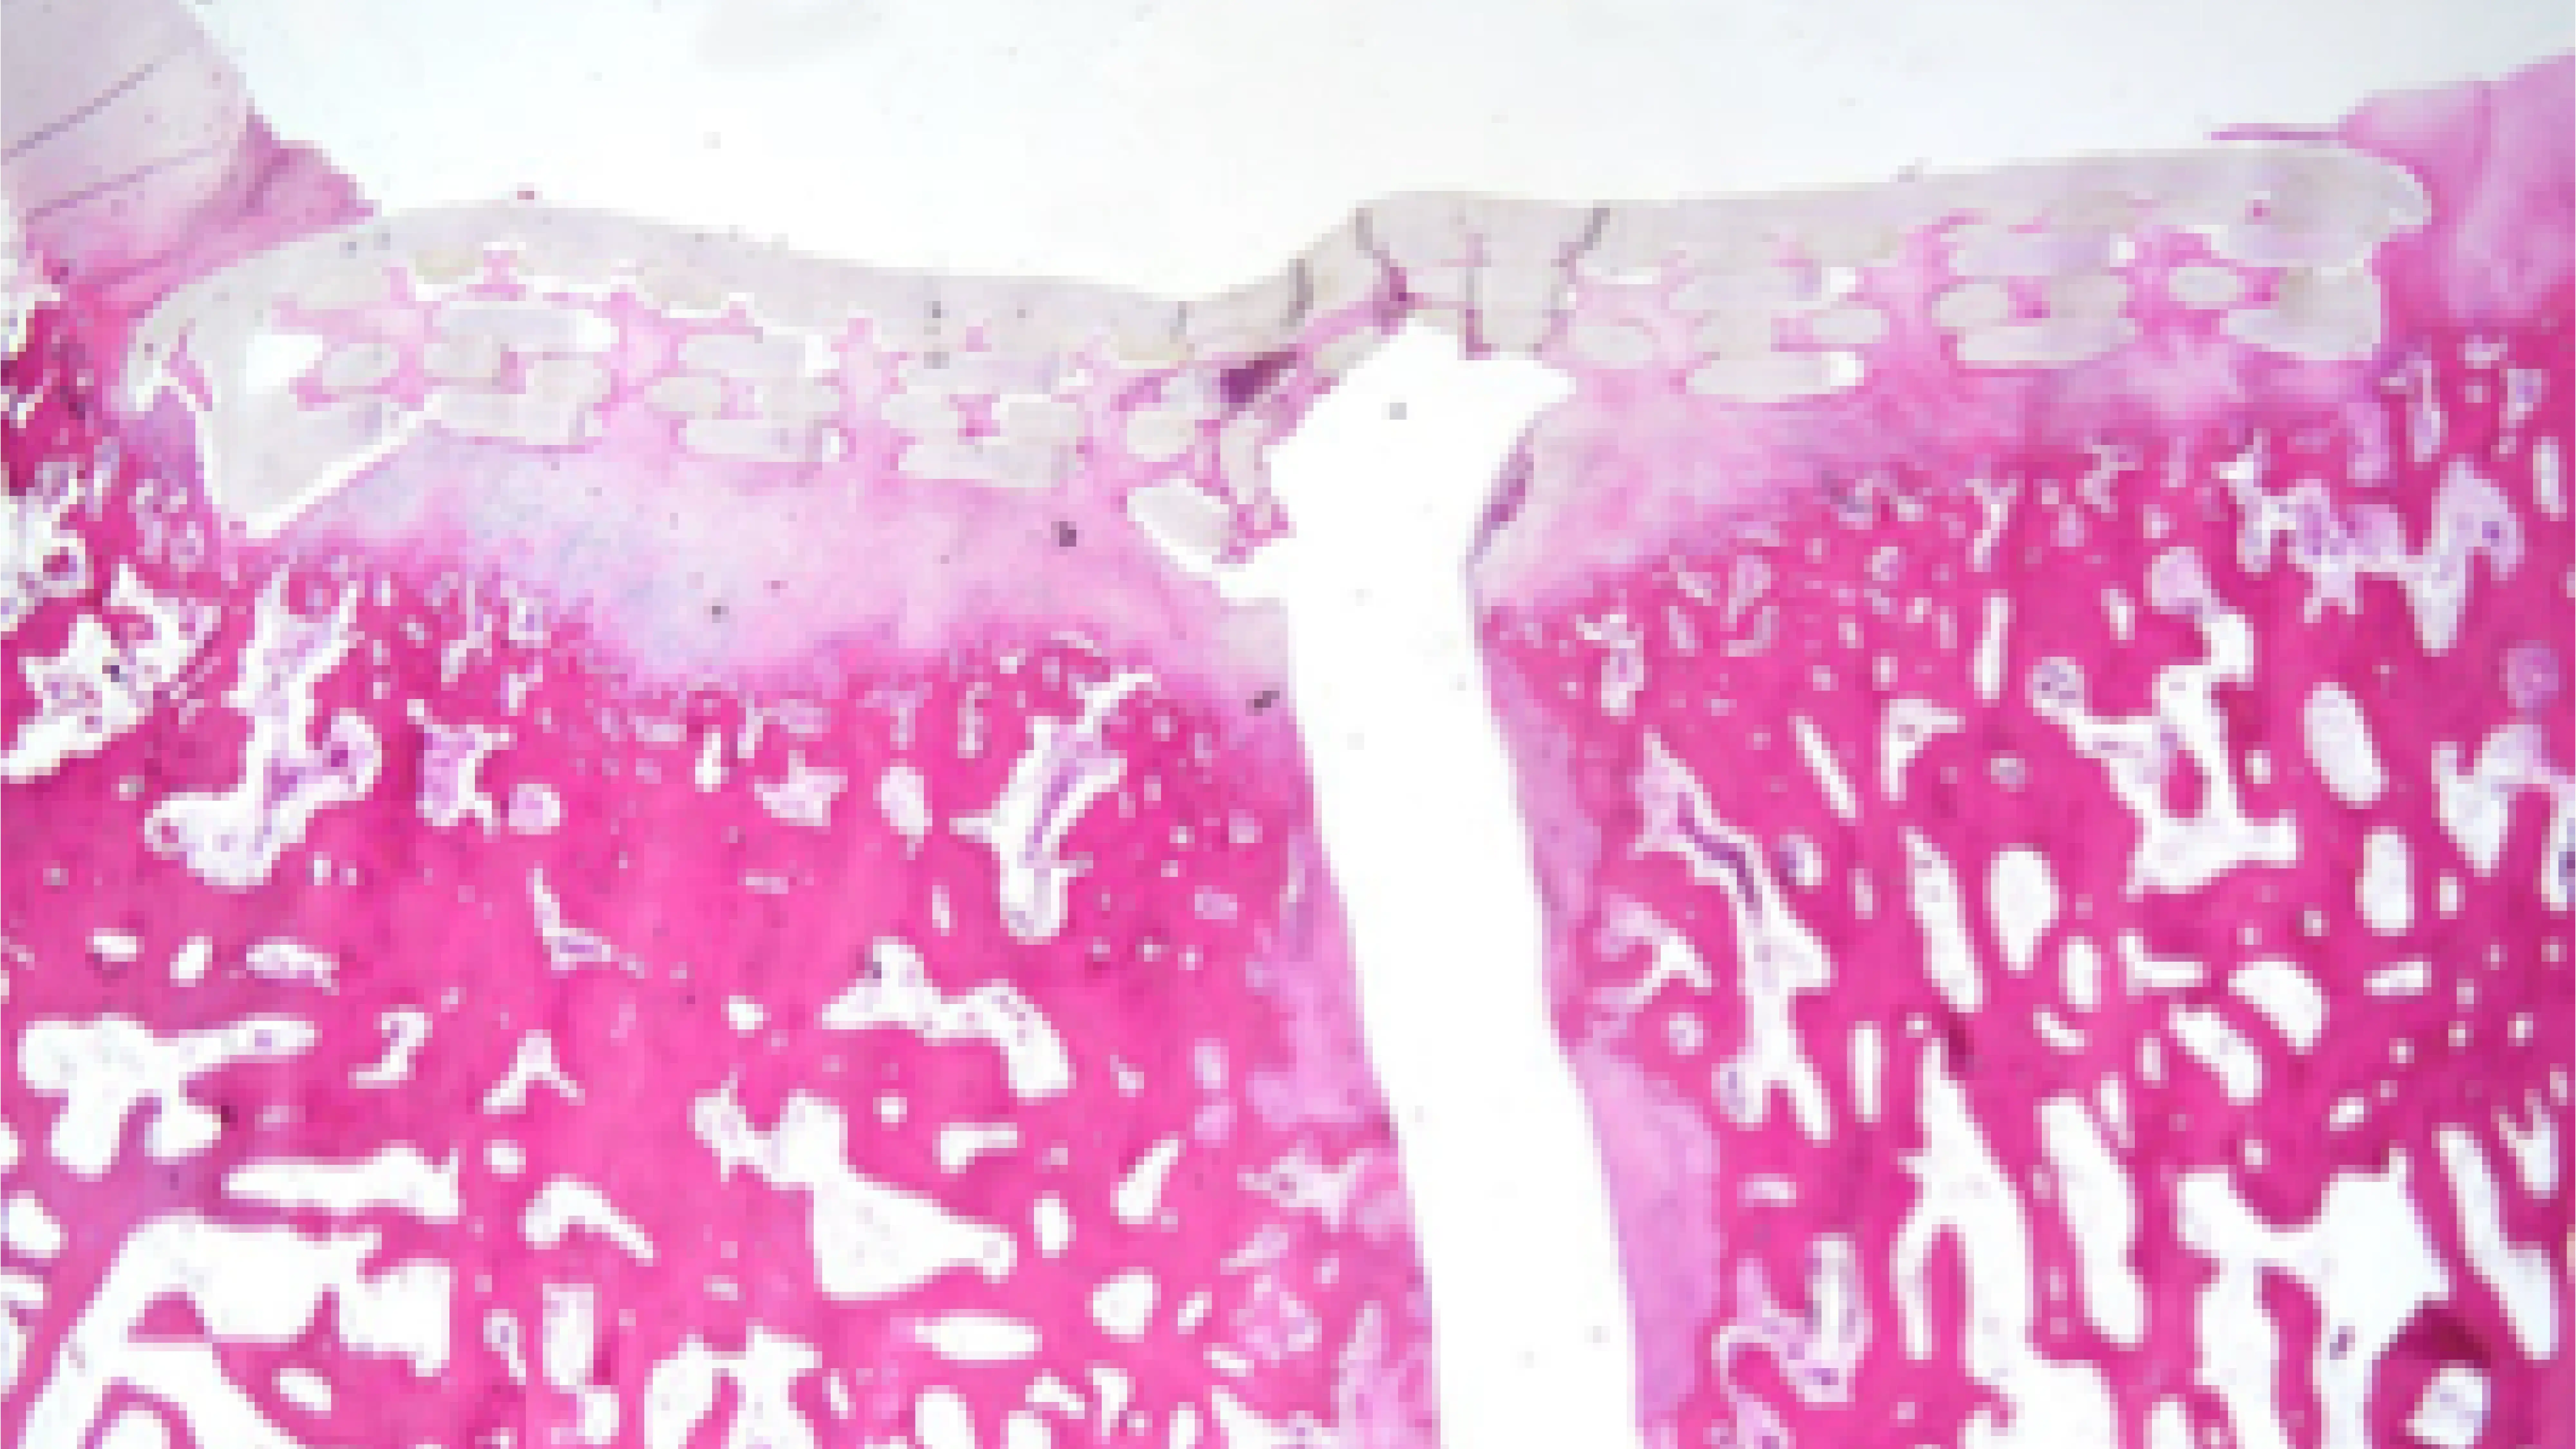

Unlike traditional methods like injection molding or machining, we use advanced 3D printing to create a complex, highly engineered structure. This design not only offers the strength needed for weight-bearing but also acts as a scaffold, supporting the growth of healthy cartilage and bone tissue over time.

The implant is designed to fit securely into the damaged area of the knee using a simple press-fit procedure. Once in place, it draws in blood and active cells from the bone underneath, supporting the body’s natural healing processes.